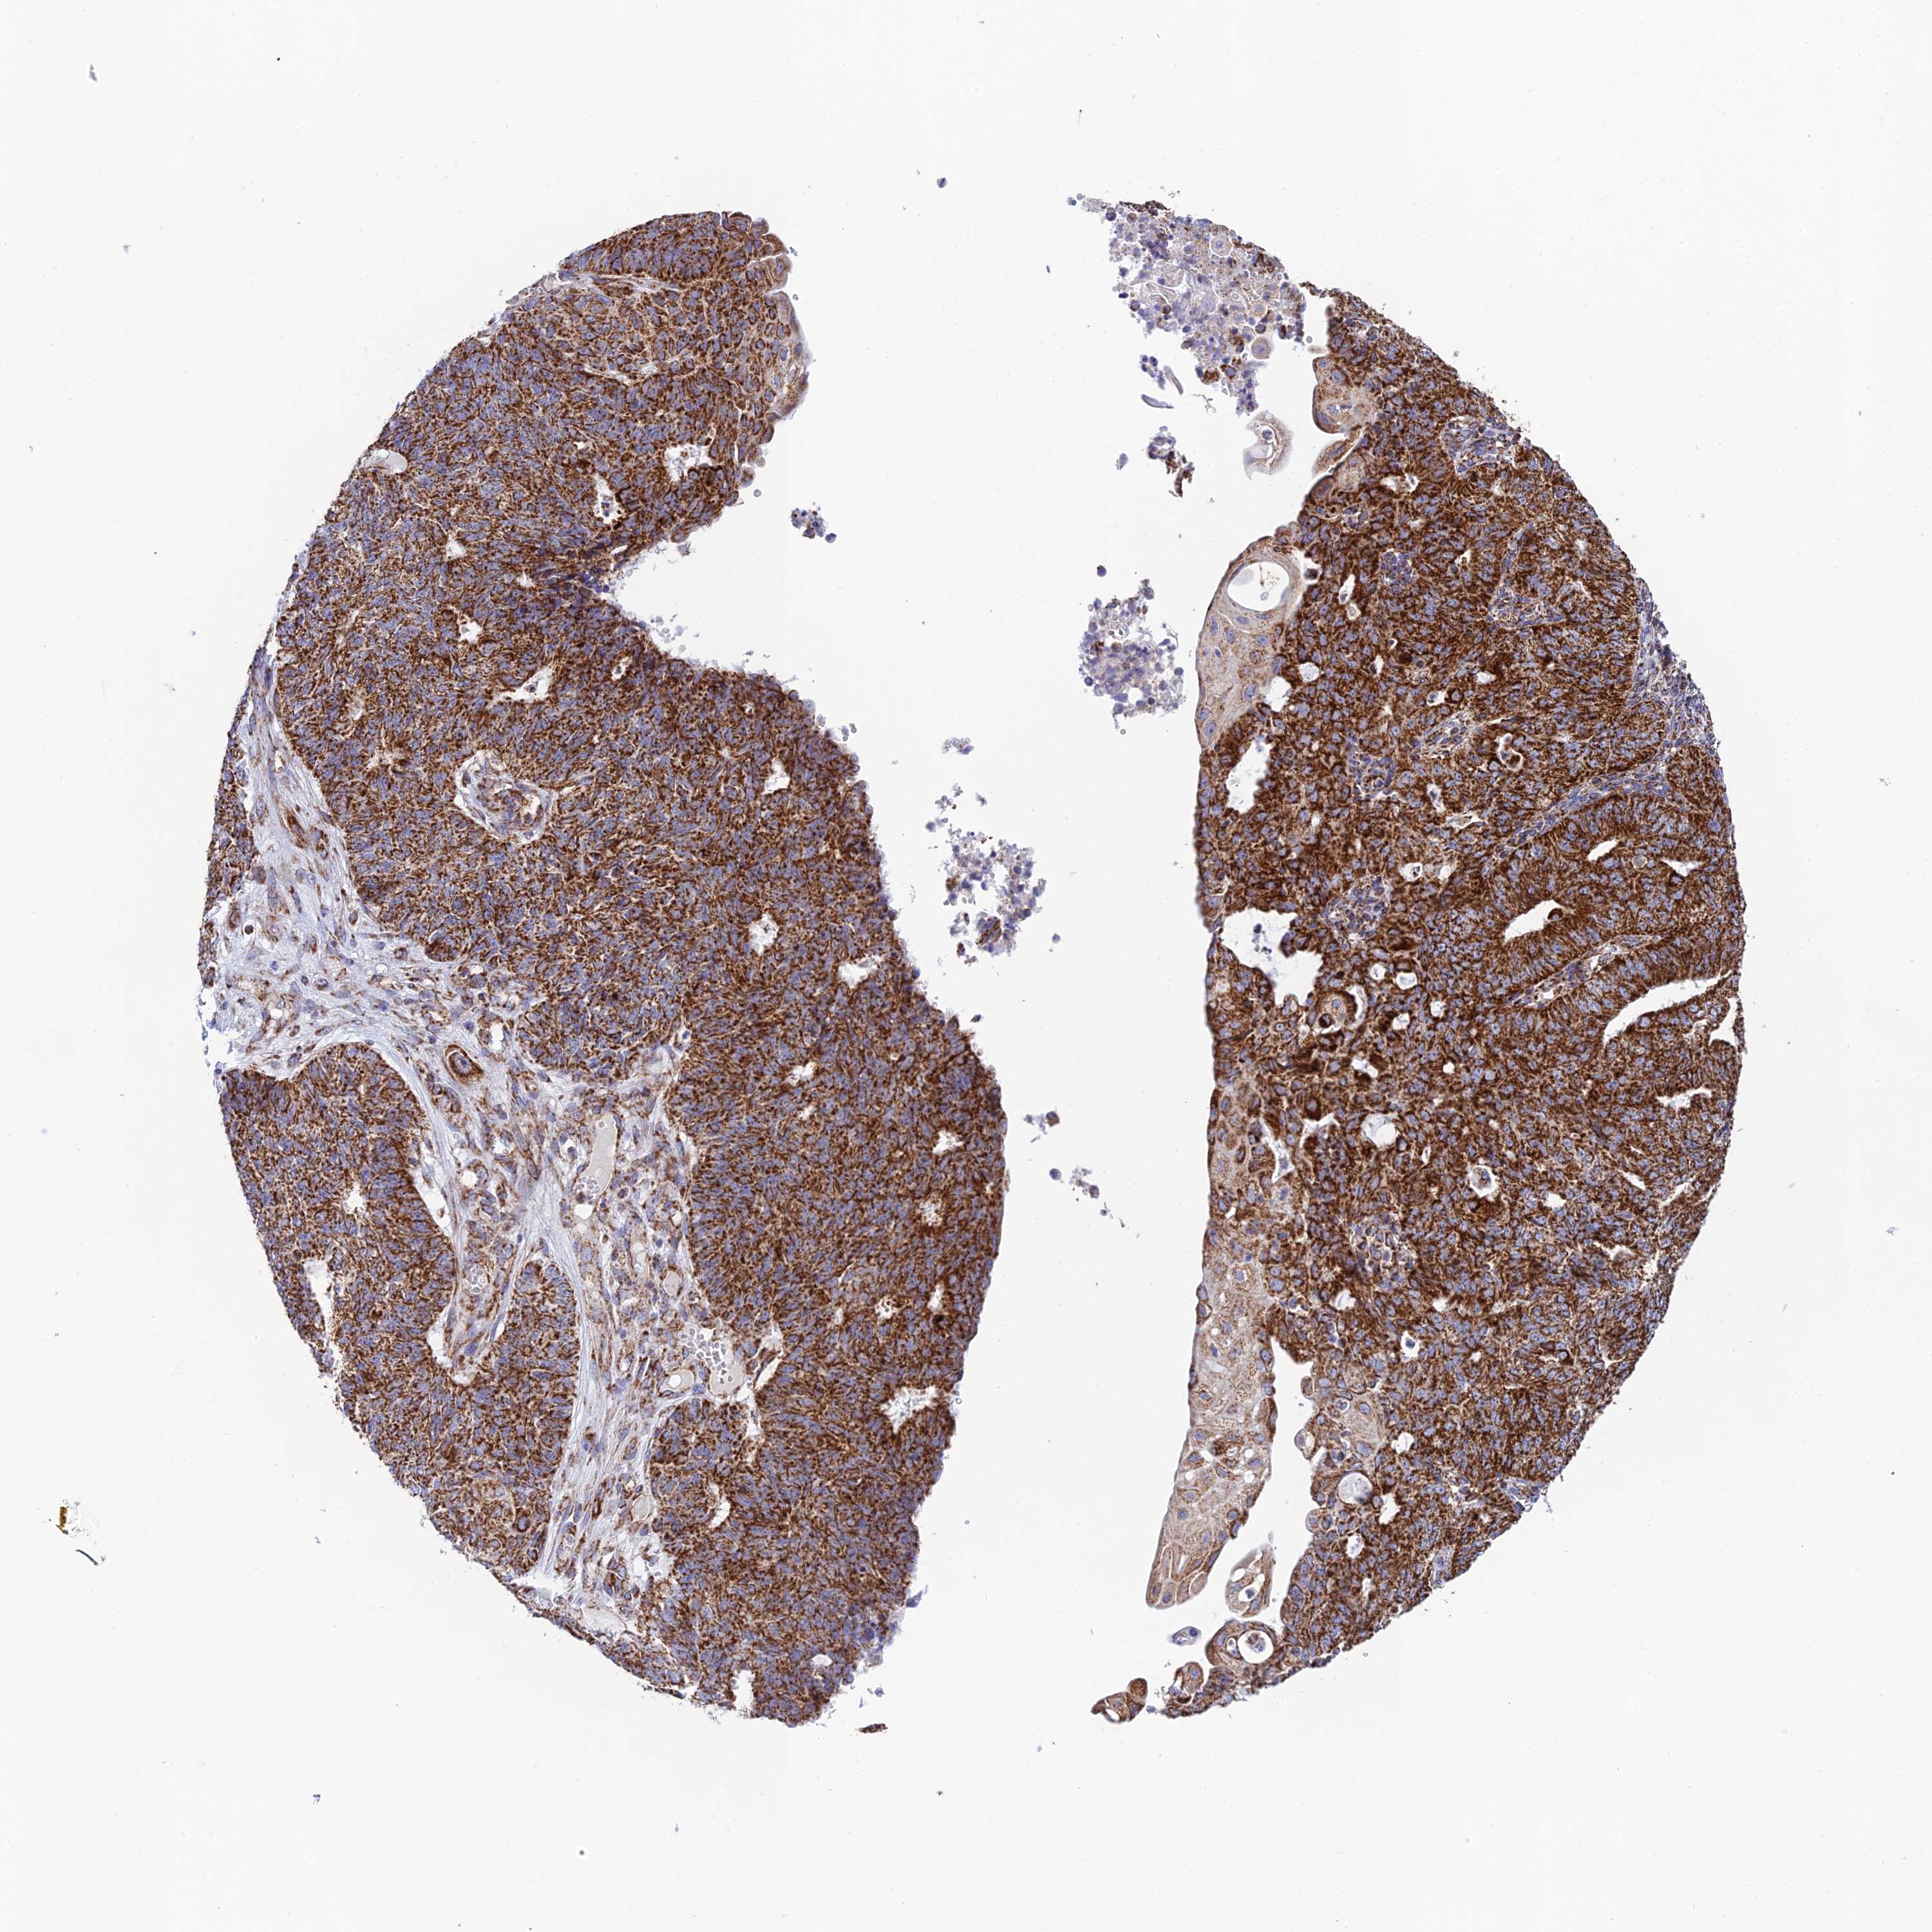

ENDOMETRIAL CANCER - Protein expressioni

A mouse-over function shows sample information and annotation data. Click on an image to view it in a full screen mode. Samples can be filtered based on level of antibody staining by selecting one or several of the following categories: high, medium, low and not detected. The assay and annotation is described here.

Note that samples used for immunohistochemistry by the Human Protein Atlas do not correspond to samples in the TCGA dataset.

Antibody stainingi

Antibody staining in the annotated cell types in the current human tissue is reported as not detected, low, medium, or high, based on conventional immunohistochemistry profiling in selected tissues. This score is based on the combination of the staining intensity and fraction of stained cells.

Each image is clickable and will lead to virtual microscopy that enables deeper exploration of all samples and also displays staining intensity scores, fraction scores and subcellular localization as well as patient and tissue information for each sample.

Antibody HPA042935

Staining

High

Medium

Low

Not detected

Intensity

Strong

Moderate

Weak

Negative

Quantity

>75%

75%-25%

<25%

None

Location

Nuclear

Cytoplasmic/membranous

Cytoplasmic/membranous,nuclear

Adenocarcinoma, NOS

Adenocarcinoma, metastatic, NOS